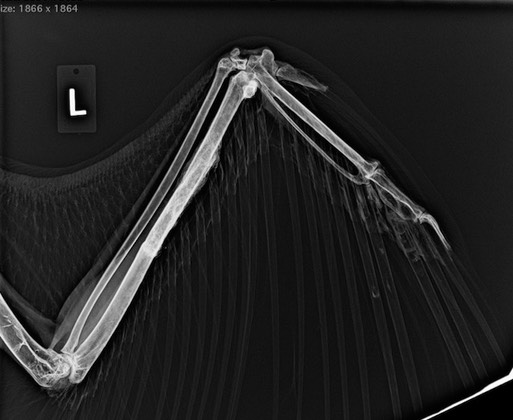

Before being moved into his new mew, we brought Patriot inside for a physical exam, blood work and radiographs. Eleven years ago he was badly injured when hit by a car. There is still evidence of his wing injury. In the radiograph below you can see the left shoulder muscles are smaller than the right shoulder muscles because he doesn’t use the left wing as much.

There is also still evidence of the healed ulna fracture.